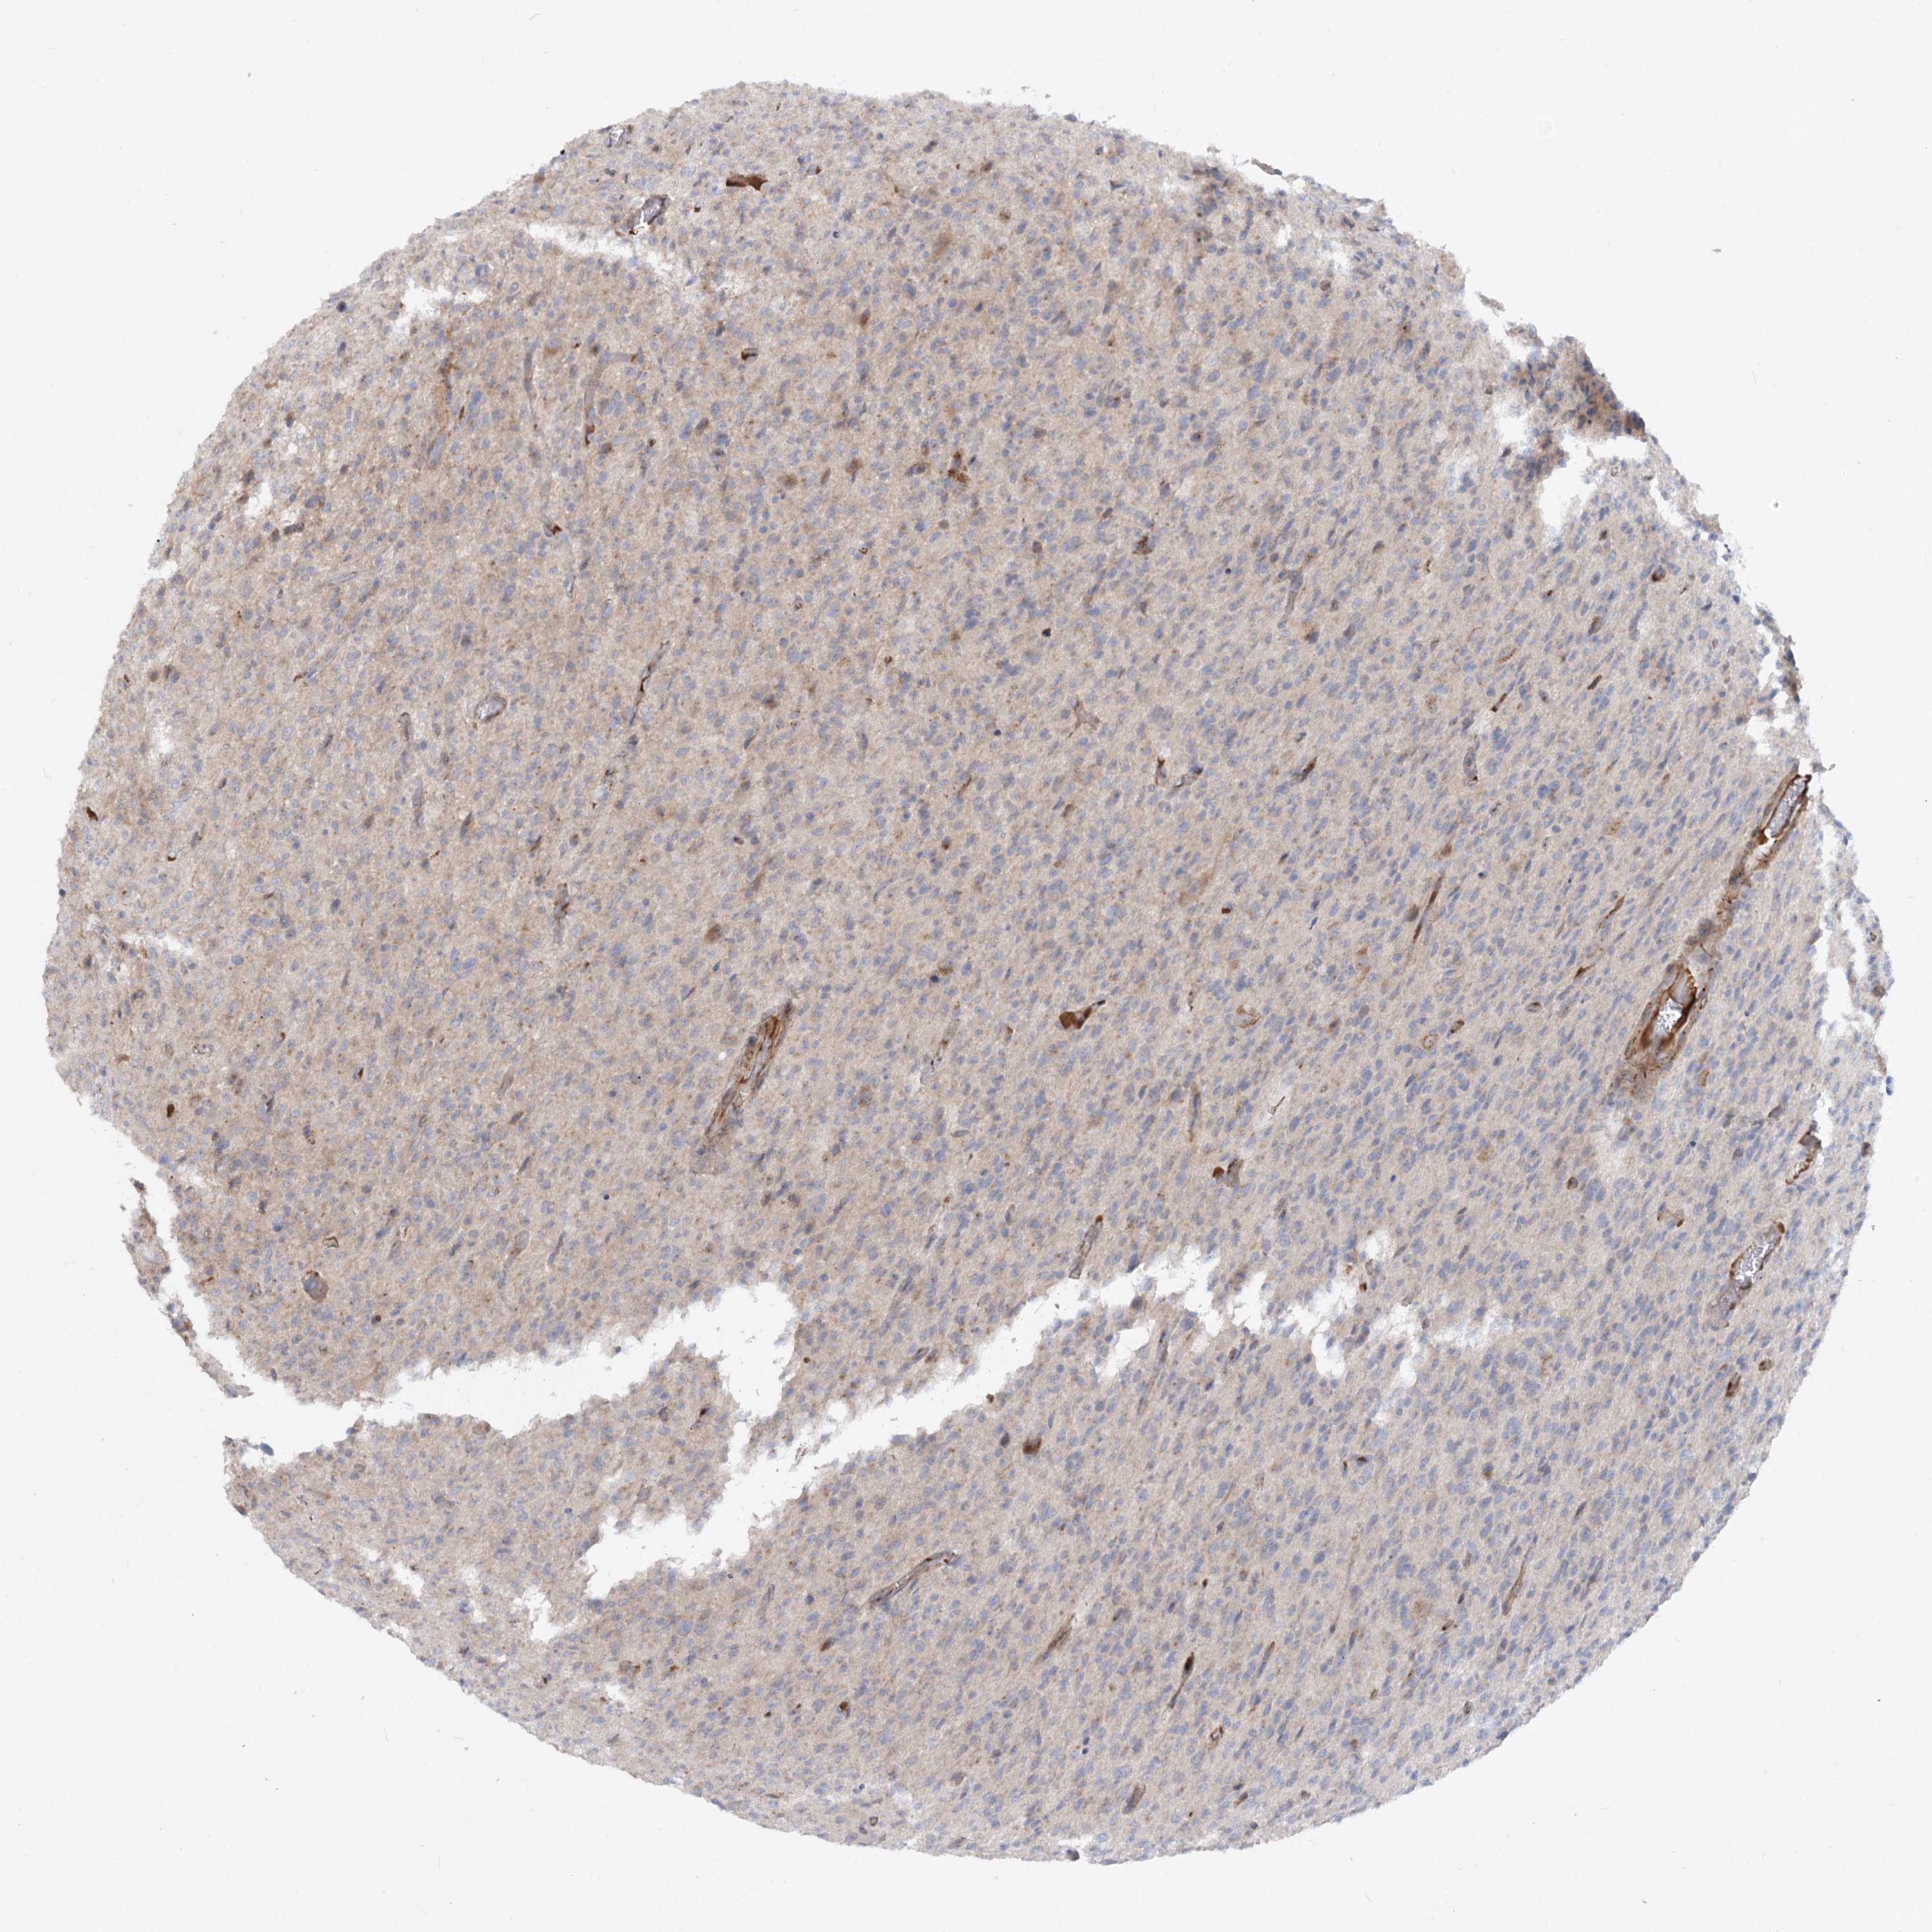

GLIOMA - Protein expressioni

A mouse-over function shows sample information and annotation data. Click on an image to view it in a full screen mode. Samples can be filtered based on level of antibody staining by selecting one or several of the following categories: high, medium, low and not detected. The assay and annotation is described here.

Note that samples used for immunohistochemistry by the Human Protein Atlas do not correspond to samples in the TCGA dataset.

Antibody stainingi

Antibody staining in the annotated cell types in the current human tissue is reported as not detected, low, medium, or high, based on conventional immunohistochemistry profiling in selected tissues. This score is based on the combination of the staining intensity and fraction of stained cells.

Each image is clickable and will lead to virtual microscopy that enables deeper exploration of all samples and also displays staining intensity scores, fraction scores and subcellular localization as well as patient and tissue information for each sample.

Antibody HPA036082

Glioma, malignant, High grade

Glioma, malignant, Low grade

Glioblastoma, NOS